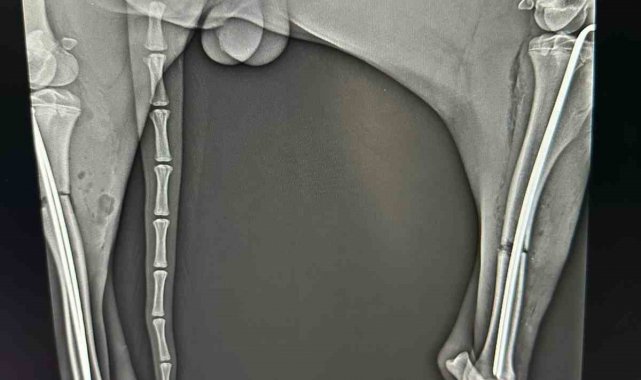

Veteriner hekimler tarafından köpeğe müdahale edildi. Yapılan tetkiklerde hayvanın sağ ve sol bacaklarında kırıklar olduğu belirlendi. Yaralı köpek, Osmaneli Belediyesi veteriner hekimi tarafından acil olarak ameliyata alındı. Başarılı geçen operasyonun ardından tedavi sürecine alınan köpeğin gözlem altında tutulduğu ve sağlık durumunun iyiye gittiği bildirildi. Yetkililer, tamamen iyileştikten sonra hayvanın doğal yaşam alanına bırakılacağını açıkladı.